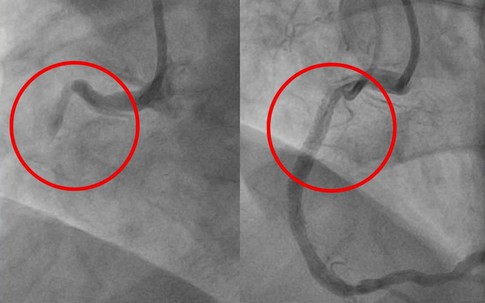

Người đàn ông 57 tuổi ngưng tim 90 phút may mắn được cứu sống, bác sĩ khuyên nên thường xuyên làm việc này để phòng bệnh